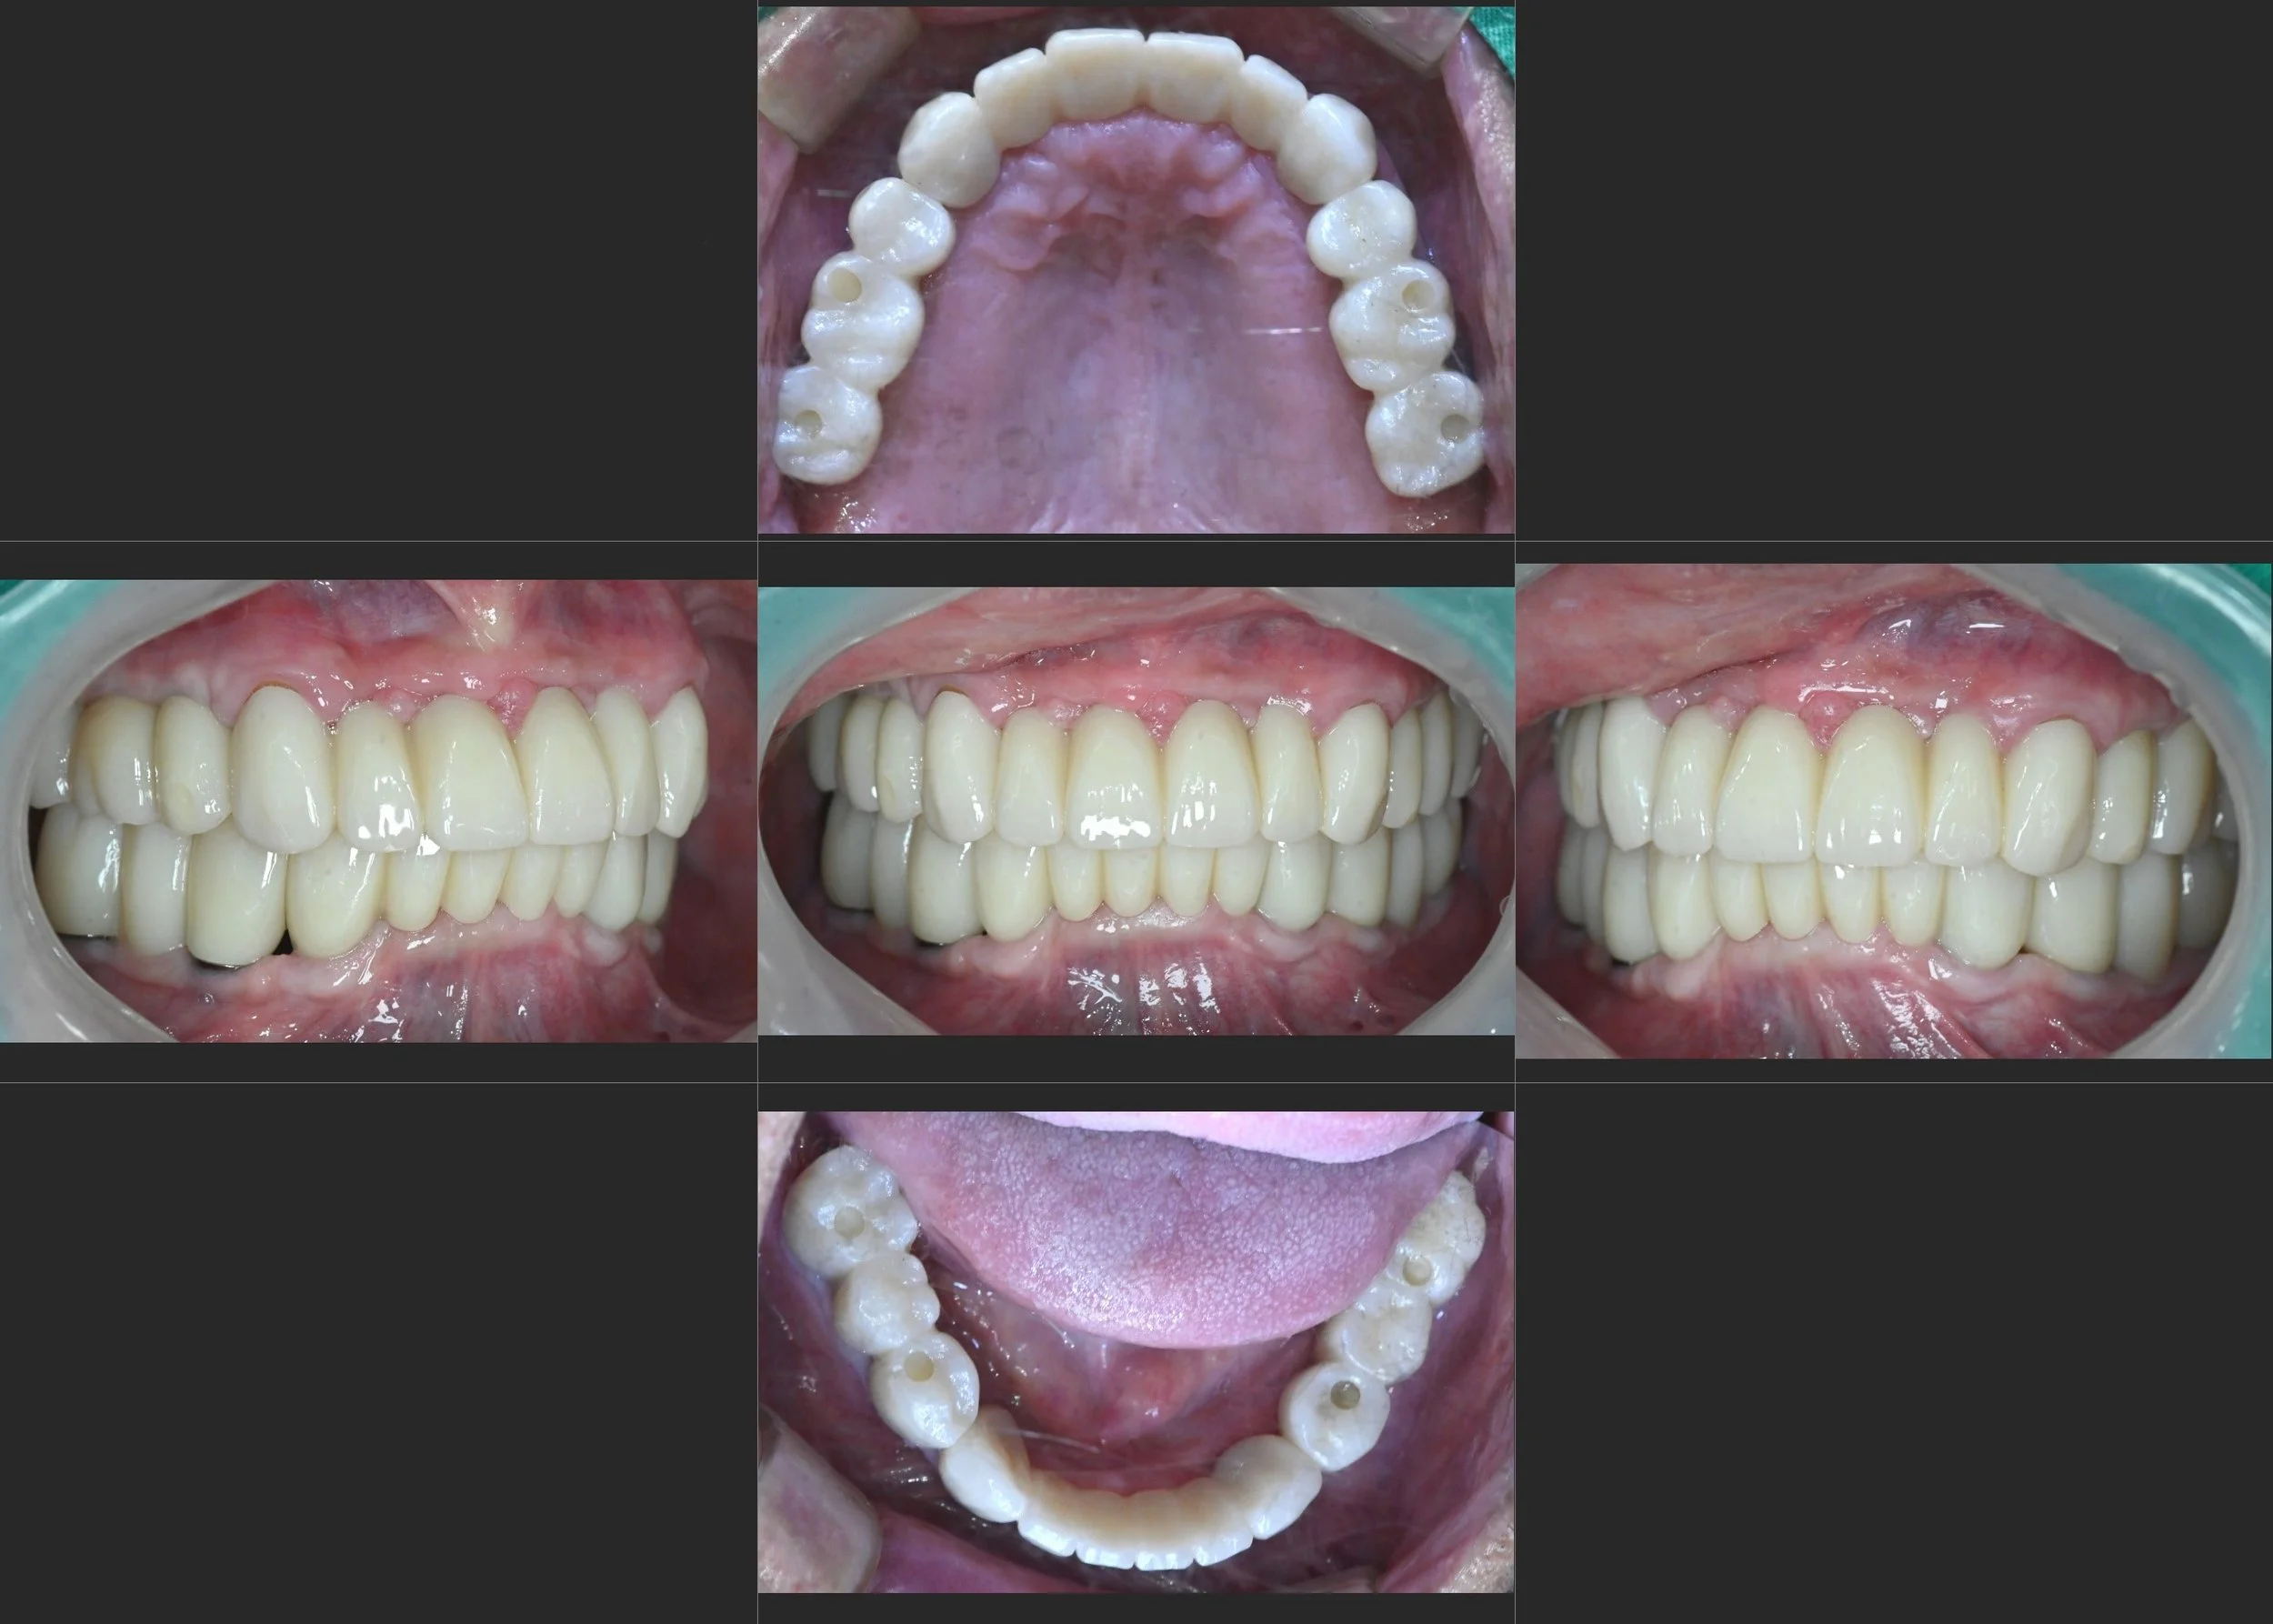

INTRA ORAL - AFTER